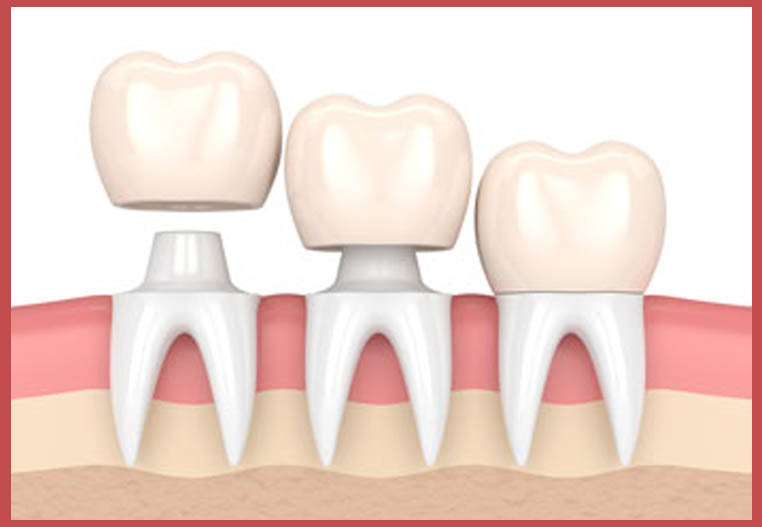

تركيب الأسنان الأمامية يمكن باستخدام زراعة الأسنان الثابتة للأسنان الأمامية في الأشخاص الذين فقدوا سن واحدة أو أكثر، حيث يتم وضع الغرسة جراحيا في فتحة في عظام الفك، وبعد أن تلتحم مع عظام الفك، وتعمل بمثابة جذر جديد للتاج الذي سيتم تركيبه، يتم تركيب التاج الذي سيحل محل السن المفقود، وهو ما يأخذنا للحديث عن أبرز المميزات التي يتم توفيرها من الزراعة في تركيا وهي كما يلي:

مرحلة التركيب النهائي

يخضع المريض خلال هذه المرحلة لعدة جلسات ضرورية، للوصول إلى التركيبة النهائيّة من التيجان، تتمثل بأخذ طبعات للفم وأخذ القوالب الخاصة للجذور المغروسة والأسنان الطبيعية الأخرى، ويفضل أن تصنع التيجان من مادة الزيركون لأن لونها طبيعي، وبعد الانتهاء من تحضير التيجان ويجب القيام بتجربة التركيبة النهائية قبل عملية تثبيتها بشكل نهائي للتأكد من ملائمتها.

تبدأ العملية بانتزاع السن المنخور أو المعطوب أو المكسور برفق وبأقل ضررٍ ممكنٍ للفك والأنسجة المحيطة، ومن ثم فحص مكان السن المخلوع وتنظيفه وتعقيمه بعدها يزرع الطبيب أساس السن الجديد في الفك بقوة دورانٍ كبيرة تضمن ثبات الأساس الجديد وبالتالي ثبات السن بعد ذلك بقية العمر، وعندها يتمكن الطبيب من تركيب تاج أو غطاءٍ أو وجهٍ مؤقتٍ للسن فوق ذلك الأساس قد يكون الأساس غير ثابت تماما وبالتالي يلجأ الطبيب عندها لجسر من الأسنان وهي رؤوس أسنان صناعية متصلة ببعضها توضع على المنطقة المصابة كلها.